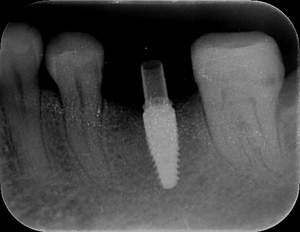

レントゲン写真

- 透過像

症例写真-1

- Befor

- After

症例写真-2

- 途中経過

| 年齢 | 50代・男性 |

| 主訴 | 右下歯が疼く |

| 治療内容 | ・右下6番インプラント ※1:FGG(遊離歯肉移植術)とは、足りない歯ぐきを上顎から上皮を切り取り移植する外科手術 |

| 治療費 | 合計:902,000円(税込) ■内訳 |

| 治療期間 | 9ヵ月 |

| 治療方針 | 右下の当該歯は歯根破折により保存不可能と診断しました。歯周疾患も伴っていたため抜歯後に骨吸収※1が大きく起こることが予測できました。チタンメッシュ併用骨再生誘導法(GBR※2)を選択しインプラント埋入と同時に行い自然な歯槽骨のラインを再現しました。またGBRを行う際にインプラント辺縁の付着歯肉の減少が起こる為、遊離歯肉移植術(FGG※3)を行い清掃性を考慮した形態に仕上げました。 ■治療方針の解説 治療した右下の歯をレントゲンで撮影したところ根本の部分に黒く写る箇所があり「根尖性慢性周囲炎※1」と診断。また歯周病も進行していました。 ※1 骨吸収・・・歯槽骨という歯を支える骨がなくなっていくこと |

| 担当者所見 | 主訴の右下だけでなく歯茎の腫れ、発赤があり不良補綴や不良充填など他にも治療箇所が多数ありました。プラークコントロールが不良であった為まずはブラッシング指導を行いセルフケアの重要性を理解していただくところからスタートしました。 右下6番の歯はインプラント治療を行なった結果審美的にも機能的にも患者様の満足を得ることができました。骨造成と歯肉移植も行なった為インプラントを支える十分な歯周組織の獲得ができたと思っております。 |